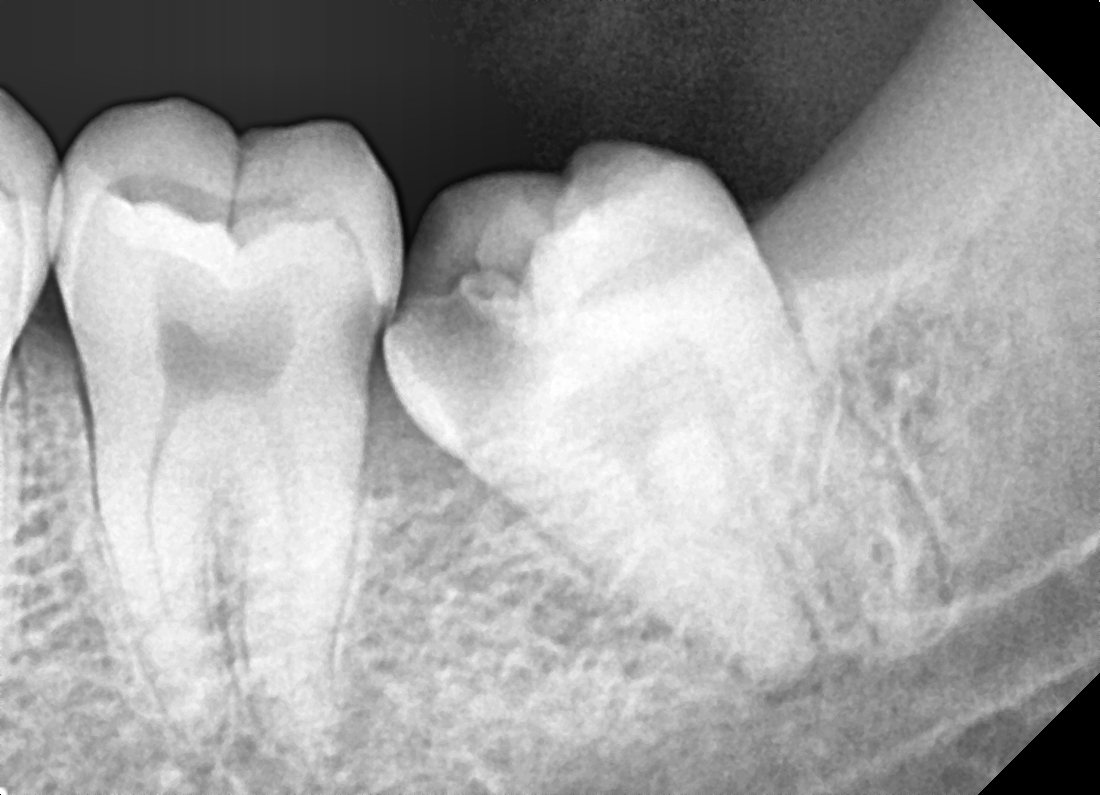

Mesioangular

After After

Before Before